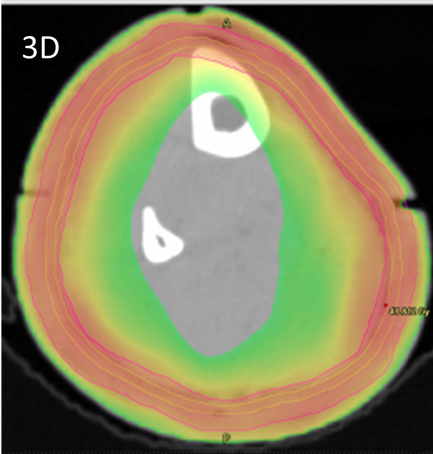

Figure 3A The RO drew the contour of the epidermis as the CTV on the planning CT, here in light green. This is usually 2-4 mm in thickness. The white triangles denote the snugly fitting vac bag. White arrows denote the joints in the 3DPB at baseline.

Figure 3B The RO also contours the PTV, in magenta, according to the national protocol7 using MIM MaestroTM planning software. The PTV was prescribed 45Gy in 25 fractions. A volume called “skin avoid” was created by having a structure, here in cyan, that extends on all the slices on which there is a PTV. It is made by being inside and 1.5cm from the PTV into the centre of the leg. The Skin Avoid structure was prescribed to receive a dose less than a mean of 25 Gy.

Figure 3C Dosimetry with dose wash minimum set at 42.5Gy showing excellent conformality and homogeneity to the PTV.

Figure 3D Dosimetry with dose wash minimum set at 25Gy showing excellent avoidance of the skin avoid structure.

Figure 3 Contouring and dosimetry.